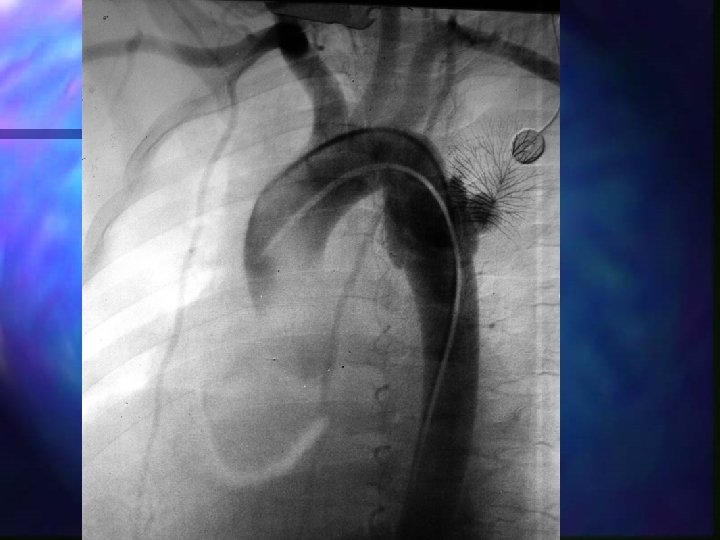

Aortic rupture Usually blunt trauma involving deceleration forces; n ~90% die within minutes n Most common site near ligamentum arteriosum n Treat like an aneurysm if still alive, blunt trauma VSA if dead (? pronounce) n Rx: surgical…poor prognosis n

Aortic rupture